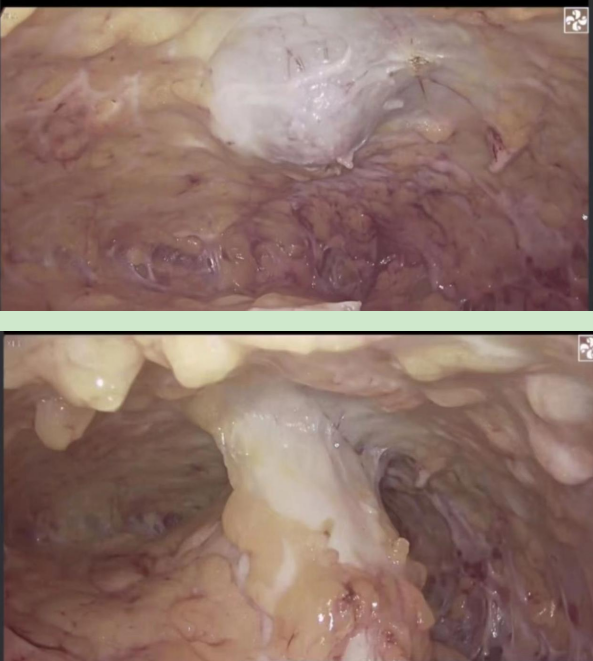

术中操作